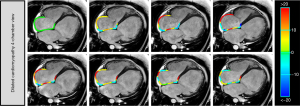

CMR-FT analysis for RA

RA deformation parameters were analyzed using commercially available software (cvi42® version 5.14.2, Circle Cardiovascular Imaging) by a researcher (Y. Gao). The basic information of cases, such as age and sex, was concealed throughout the CMR-FT analysis. RA endocardial and epicardial borders were manually traced in the 4-chamber views using a point-and-click approach at the minimum RA volume after atrial contraction (11). The superior vena cava and RA appendage were excluded from the RA endocardial contours and the automated tracking algorithm was subsequently applied. Tracking performance was visually checked to ensure accurate tracking of the RA myocardium and the initial contours were manually adjusted when necessary (Figure 1). The longitudinal RA strain and SR values were obtained using feature tracking analyses in the 4-chamber views. We analyzed 3 aspects of RA strain and SR (22): reservoir strain and peak positive SR (εs and SRs, corresponding to atrial reservoir function during RV end-systole), conduit strain and peak early negative SR (εe and SRe, corresponding to atrial conduit function during RV early diastole), and booster strain and peak late negative SR (εa and SRa, corresponding to atrial booster pump function during RV late diastole) (Figure 2).